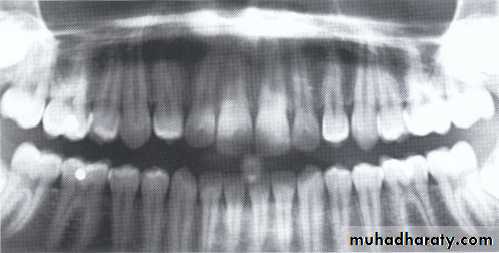

Dentin dysplasia, type I. panoramic & periapical films of the same case show the short and poorly developed roots, obliterated pulp chambers and root canals, and periapical inflammatory lesions.